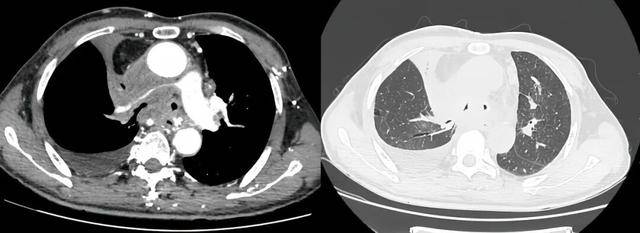

术前受压变窄的右肺动脉和中央气道

“这相当于同时扼住了‘呼吸道’和‘血管通路’,是导致李大爷濒临呼吸衰竭的直接原因。”接诊的医院介入科副主任高志解释到,中央气道是空气进出肺部的“主干道”,一旦狭窄,病人便会出现呼吸困难、窒息感,而肺动脉是心脏向肺部泵送血液进行氧气交换的“唯一途径”,如果被压迫变窄,病人全身的氧气供应会受到严重影响。二者同时发生,病情呈几何级数恶化,传统内科治疗手段回天乏术,外科手术则因肿瘤侵犯风险极高。

面对这一严峻挑战,一场与时间赛跑的生命救援迅速启动,由医院介入科、呼吸与危重症医学科、麻醉科组成的多学科诊疗团队紧急集结。会诊室专家们审阅着影像资料上触目惊心的狭窄部位,深知这是一个“牵一发动全身”的极高风险手术。麻醉是之一项挑战,患者基础状况差,在气道严重狭窄下进行插管全麻,本身就可能引发窒息。经过周密论证,一个大胆而精细的“双轨救援”方案最终确定:通过麻醉,分别为患者施行“气管支架置入术”和“肺动脉覆膜支架置入术”,用微创的方式一次性打通两条核心生命通道。